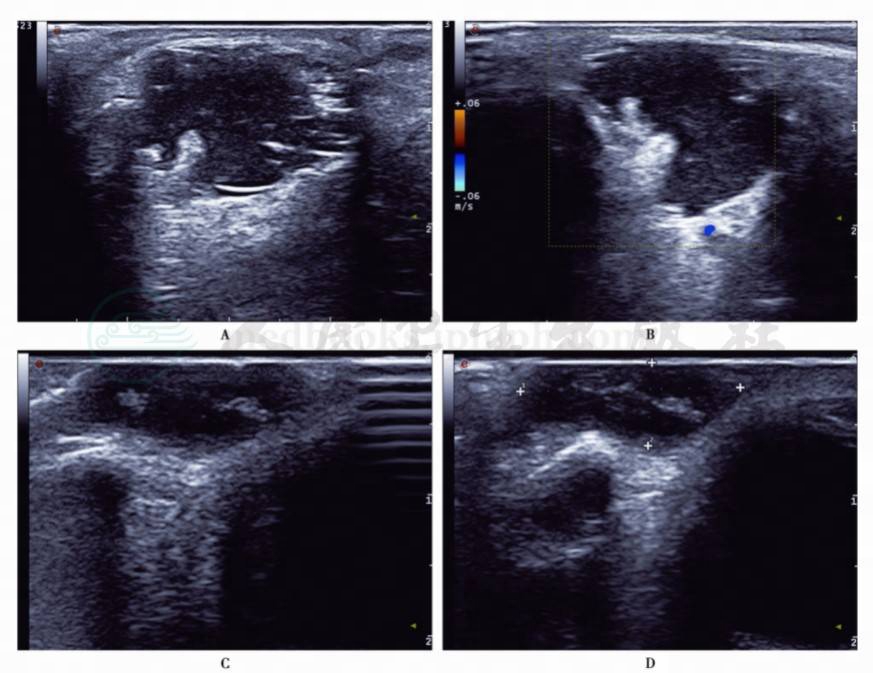

图3眼眶表皮囊肿2例

A.左眼眶外侧囊实性肿块;B.肿块内无血流信号;C、D.眼眶外侧混合性肿块,边界清楚